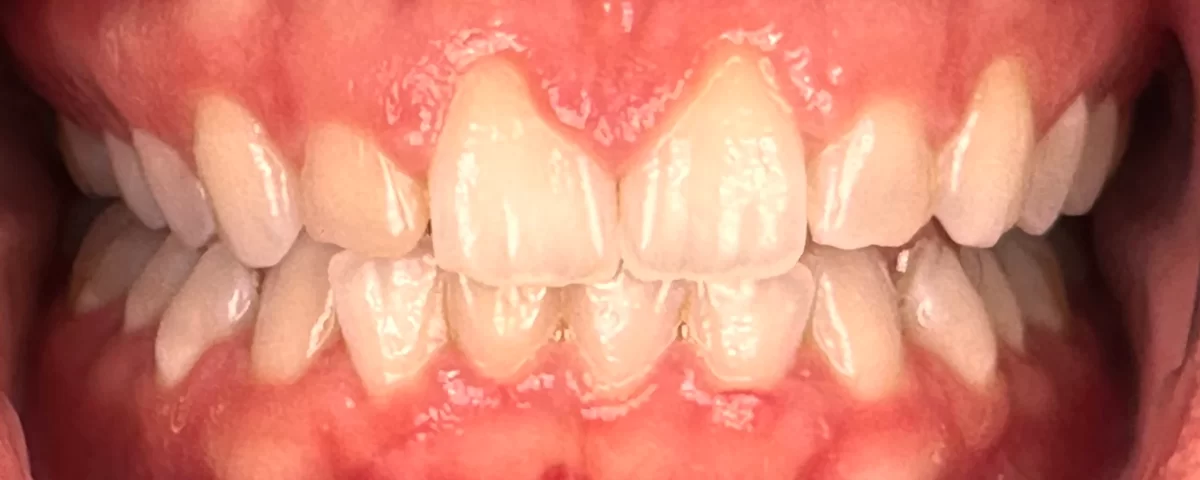

2025-06-16A confident smile can make a world of difference in self-esteem and social interactions. However, for some individuals, excessive gum display—commonly referred to as a "gummy smile"—can make them feel self-conscious. This case study highlights how crown lengthening can enhance smile aesthetics by exposing more tooth structure and creating a balanced gum contour.

Our patient, a female in her mid-20s, had long been self-conscious about her gummy smile. Her upper front teeth appeared short and squatty due to excessive gum tissue. Additionally, her gum line had an irregular and uneven contour, making her hesitant to smile widely in social and professional settings. She sought a solution that would provide a more proportionate and aesthetically pleasing smile.

Recovery was remarkably smooth. The patient reported no post-operative pain once the local anesthesia wore off. The gum tissue exhibited mild inflammation for a few days but quickly settled down, revealing a more even and aesthetically pleasing contour. The final outcome showcased:

- Increased Tooth Display: More of the natural tooth structure was visible, creating a balanced smile.

- Harmonized Gum Line: The gum contour was even and symmetrical, complementing the patient’s facial aesthetics.

- Enhanced Confidence: The patient was thrilled with the transformation, expressing newfound confidence in her smile.

In aesthetic dentistry, the harmony between the "white" (teeth) and the "pink" (gum tissue) is crucial. The teeth need to be properly framed by the gum tissue for a smile to look natural and attractive. Crown lengthening not only improves the proportions of the teeth but also ensures that the gum line enhances, rather than detracts from, the overall smile.